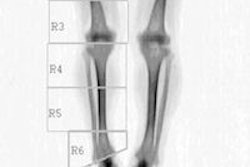

The Norwegian study aimed to determine if greater weekend computer use is associated with reduced BMD. They examined 463 girls and 484 boys 15-18 years old using dual-energy x-ray absorptiometry (DEXA), also collecting data on lifestyles via questionnaires and interviews, and adjusted for myriad factors including age, sexual maturation, BMI, leisure time activity, smoking, alcohol, cod liver oil, and soda consumption to tease out associations between BMD and screen time.